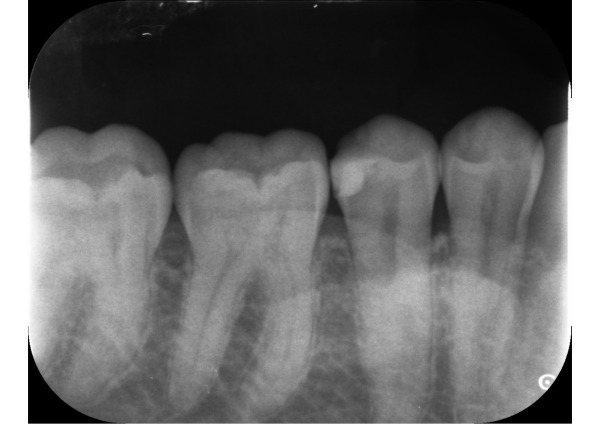

患者様は、これまで他院にて1年に一度の検診を受けられていたそうです。今回当院にて検診の継続を希望され、お口を見てみると右下の詰め物が欠けて、歯の中が虫歯になっていました。

1日目 虫歯を除去し、プラスチックで裏層後、型取りをしました。

2日目 ジルコニアインレーを接着性セメントで装着しました。